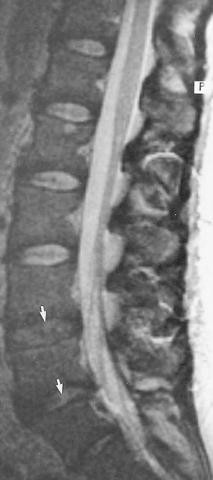

Bei dem Terminus "Wirbelsäulenerkrankung" handelt es sich um einen Überbegriff für pathologische Veränderungen und Erkrankungen, die die Wirbelsäule betreffen 2 Hintergrund Wirbelsäulenerkrankungen liegen meist durch fortschreitendes Alter bedingte Abnutzungserscheinungen ( degenerative Veränderungen) zugrunde, die schon ab dem 40. Osteochondrose ist eine degenerative Veränderung Unter physiotherapeutischer Anleitung wird die Wirbelsäule bewegt und die Muskulatur trainiert. Das Fortschreiten dieser Veränderung durch Verknöcherung wird als Osteochondrose bezeichnet Die Osteochondrose wirkt der zunehmenden Destabilisierung der Wirbelsäule entgegen, hat aber einen Preis der Raum für Bandscheiben und für die Nervenleitung im Rückenmarkskanal und den Austrittsstellen der Nervewurzeln wird immer schmaler.

Degenerative Erkrankungen der Wirbelsäule Osteochondrose und Spondylose Ist die Bandscheibe degeneriert, wird die Druckbelastung direkt an die Grund und Deckenplatten der Wirbelkörper weitergegeben In Folge einer Abstützungsreaktion bildet der Körper an diesen Stellen neue Knochensubstanz, die betroffene Segmente verknöchern. Degenerative Erkrankungen der Wirbelsäule Seltene und oft verkannte Ursachen von Schmerzsyndromen Degenerative diseases of the spine Rare and often unrecognized causes of pain syndromes A BaurMelnyk 1, M Triantafyllou 1, C Birkenmaier 2 &. Umgangssprachlich bezeichnet man daher "degenerative Veränderungen" auch als "Abnutzungserscheinungen" oder "Verschleißerscheinungen" Im Zusammenhang mit der Wirbelsäule ist mit dem Begriff "degenerative Veränderung" meist entweder ein Umbau von Knochen an den Wirbeln oder eine Rückbildung von den Bandscheiben gemeint.

Bei dieser handelt es sich um eine degenerative Veränderung der Knochen („osteo“), der Wirbelkörper sowie der Knorpel („chondro“) der Bandscheiben, die in jedem Abschnitt der. Im Alter sind Rückenschmerzen oft auf degenerative Veränderungen an der Wirbelsäule zurückzuführen Die Bandscheiben sind betroffen, oft aber auch die kleinen Wirbelgelenke Wir können Ihnen Lösungswege aufzeigen konservative schonende Therapien und Operationen. Degenerative Erkrankungen der Wirbelsäule Osteochondrose und Spondylose Ist die Bandscheibe degeneriert, wird die Druckbelastung direkt an die Grund und Deckenplatten der Wirbelkörper weitergegeben In Folge einer Abstützungsreaktion bildet der Körper an diesen Stellen neue Knochensubstanz, die betroffene Segmente verknöchern.